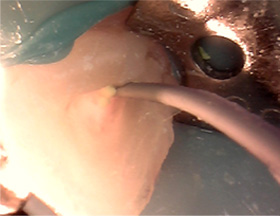

오른쪽 어금니 염증으로 내원한 40대 환자입니다. 치석이 잇몸 안쪽으로 진행되어 마취 후 큐렛을 진행 했습니다.

큐렛은 일반 스케일링보다 잇몸 속 더 깊숙이 있는 치석, 염증을 제거하는 치료입니다.

잇몸 사이 치석과 낭종

큐렛으로 낭종 및 치석제거